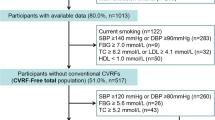

Vascular structure and function were evaluated through measurement of Carotid Intima Media Thickness by High Frequency Ultrasound (hfCIMT) and Pulse Wave Velocity by ultrafast ultrasound imaging (ufPWV), as summarized in Fig. 1.

Pictorial representation of study protocol. Participants underwent recording of hfCIMT and ufPWV at the same location on the carotid artery in a supine, resting position. Inserts below in-figure text show sample raw data of hfCIMT (top) and PWN-DN (bottom). PWV is calculated from the slope of the position-time graph, as determined by radon transform, depicted by the black line at the 400s mark

Carotid intima media thickness via high frequency ultrasound (hfCIMT)

hfCIMT was measured using the VevoMD ultrasound system (Fujifilm, Toronto, Canada) with a 22 MHz transducer for bilateral imaging of the common carotid artery. The common carotid arteries were imaged 1 cm proximal to the carotid bulb in a long axis view illustrating the largest lumen dimension with good distinction between structural interfaces and no compression of the blood vessel during acquisition. All image acquisitions were measured by the same operator (W.H.) [25]. The mean of three measurements were used for analysis.

Pulse wave velocity via ultrafast ultrasound imaging (ufPWV)

The left common carotid artery was assessed by ultrafast ultrasound imaging (UUI) using a programmable ultrafast ultrasound system (Vantage 256, Verasonics, Kirkland, WA, USA) equipped with a GE 11-L linear transducer (GE Vingmed, Horten, Norway) as previously described [26, 27]. Briefly, the probe was placed in longitudinal orientation ~ 1–2 cm proximal to the common carotid artery bifurcation, and UUI acquisition was automatically triggered by the peak of the R wave on ECG. Raw data was beamformed into In-phase/Quadrature datasets (IQ) and processed using MATLAB (The MathWorks Inc., Natick, MA, USA). Each acquisition lasted 709 ms and covered 1 cardiac cycle. ufPWV was determined offline on MATLAB using our previously published post-processing methods [26, 27]. Two pulse waves are found within a cardiac cycle: one created by the pressure wave of blood pumped out at the beginning of systole (systolic foot, PWV-SF), and one formed by the pressure differential from the aortic valve closing at the end of systole (dicrotic notch, PWV-DN). PWV-SF and PWV-DN were measured and recorded at least twice for each participant, with the average value used for each in analysis.